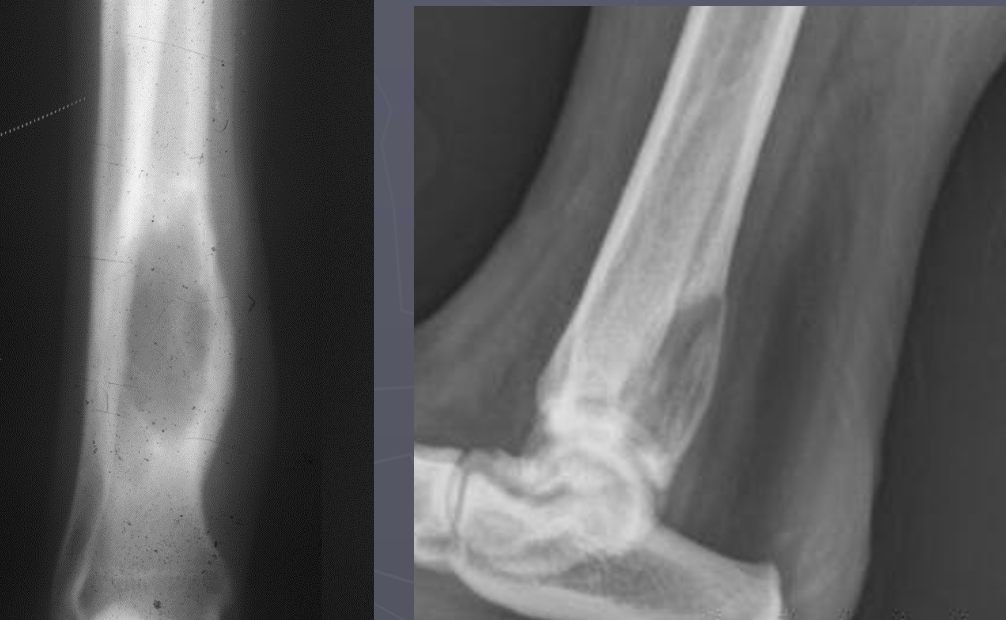

What is seen in these radiographs?

solid periosteal reaction